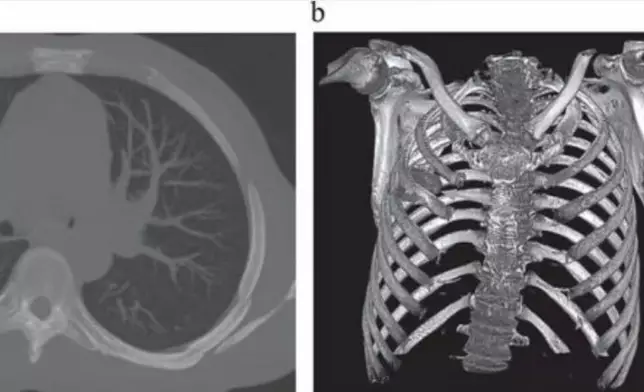

醫生隨後為男子安排X光檢查,結果發現胸腔內竟藏有一件利刃狀金屬異物,自肩胛骨位置刺入,四周被膿液及壞死組織包圍,令醫療團隊大為震驚。在醫生追問下,患者回憶起 8 年前曾捲入一場激烈衝突,當時臉部、背部、胸部及腹部均遭多處刀傷。然而,由於當地醫療資源匱乏,他僅接受表層傷口縫合,並無進行深入檢查,之後多年也未曾出現異常症狀。

經專科安排,男子立即接受手術移除刀片,術後恢復情況理想,於 10 天後順利出院。醫療團隊表示,「患者身體成功將異物包覆在纖維囊內,限制了發炎和組織損傷」,但乳頭開始流膿已是嚴重併發症前兆。他們強調,這枚殘留刀片原可造成致命風險,並呼籲提升資源不足地區的創傷處理能力及醫療設備,以免類似情況再度發生。目前,相關病例已刊載於《外科病例報告期刊》(JSCR)。